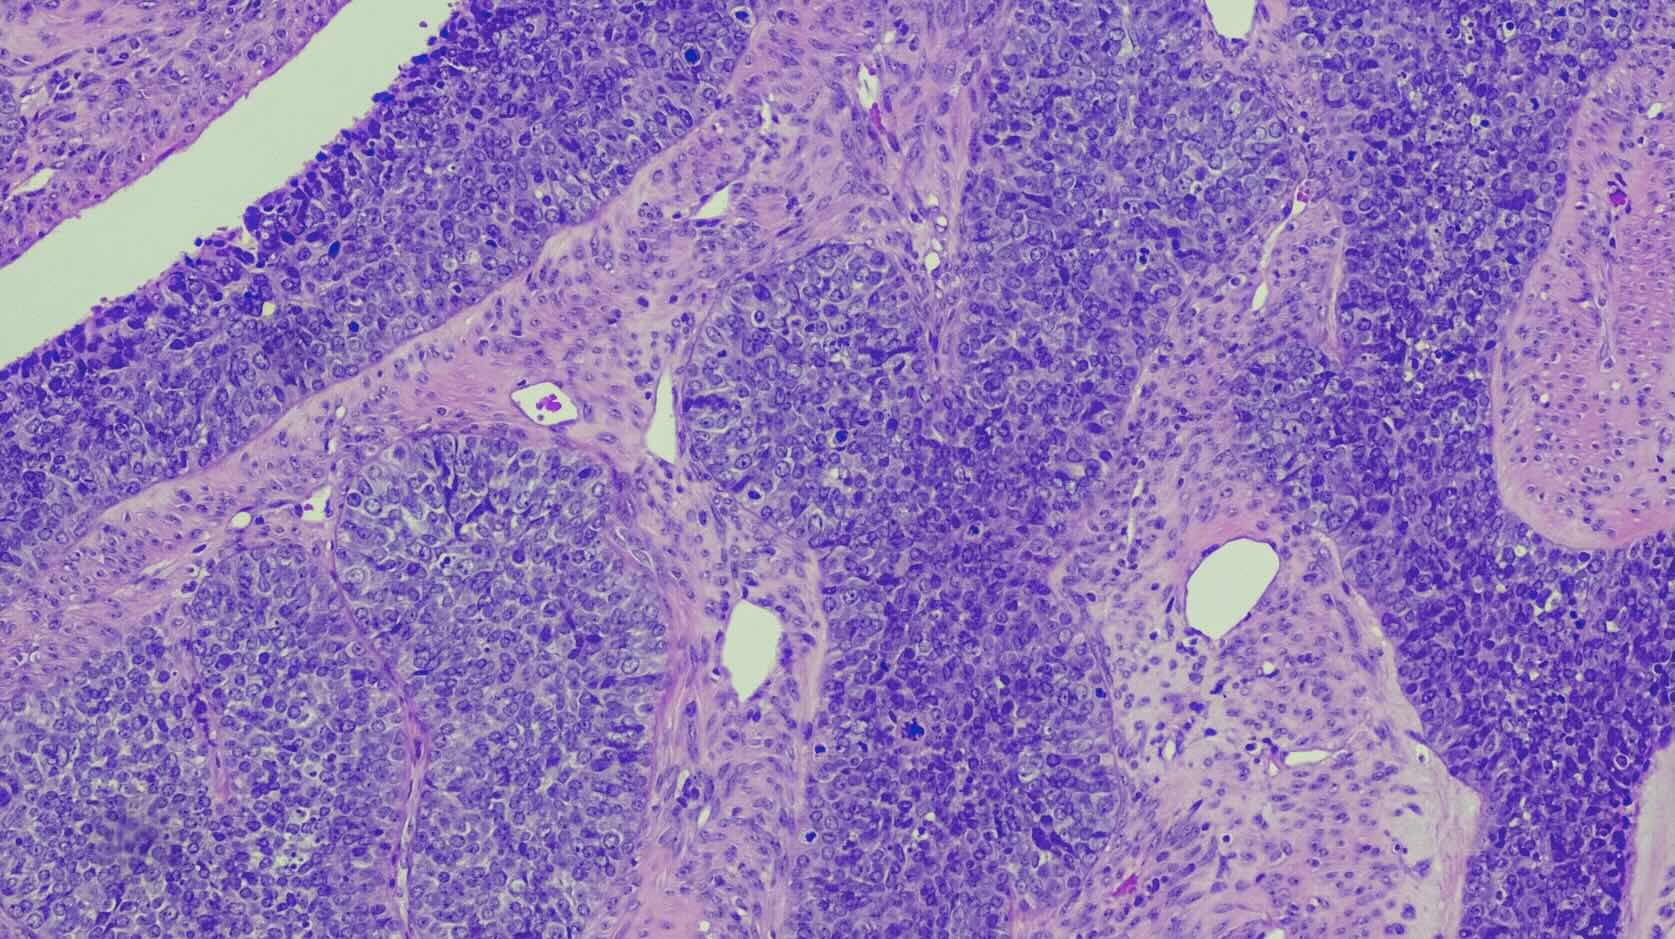

Peter Mac researchers have discovered a powerful new drug combination that could offer hope to children and adults with certain subtypes of acute myeloid leukaemia (AML).

The treatment works by using a combination of two agents, a Menin inhibitor, revumenib, which is already being used to treat AML, and a new drug, called PF-9363, that is currently in clinical development and being trialled in breast cancer.

Peter Mac PhD student Shellaina Gordon said PF-9363 blocks the KAT6/7 enzymes which help cancer cells grow and survive so when used with a Menin inhibitor, the two drugs rapidly stop the leukaemia cells from multiplying and eventually lead to cancer cell death.